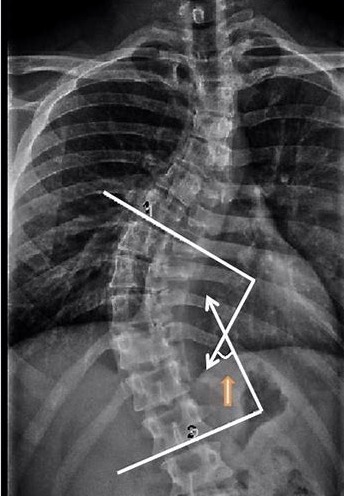

Cobb's angle(科布角)

布骨脊柱侧弯矫正中心 ,2020-02-27

Cobb角 定义:Cobb角被用作标准测量来确定和跟踪脊柱侧弯的进展。Dr John Cobb 在1948年发明了这种方法。存在意义:Cobb角帮助医生决定需要什么样的治疗。 .....